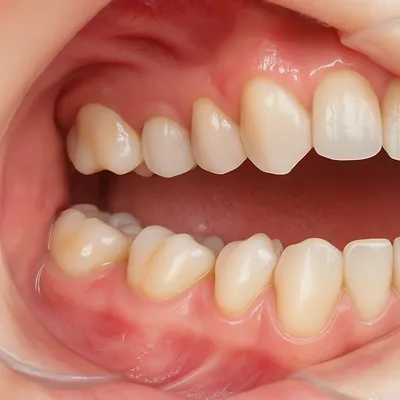

نکات تکمیلی درباره دندان عقل

دندان عقل معمولاً آخرین دندان دائمی است که بین سنین ۱۷ تا ۲۵ سالگی رویش میکند. همین زمان دیرهنگام رویش، دلیل اصلی بسیاری از مشکلات شایع مانند نهفتگی، التهاب لثه، عفونت و فشار به دندانهای کناری است.

شمارهگذاری باعث میشود ارتباط بین بیمار و دندانپزشک شفافتر باشد و درک بهتری از علت درد یا لزوم جراحی ایجاد شود. در واقع، دانستن اینکه دندان عقل شماره چند است به بیمار کمک میکند هم مشکلات احتمالی را سریعتر بشناسد و هم روند درمان را با اطمینان بیشتری دنبال کند.

نمای بالینی واضح مولر سوم در دهان باز